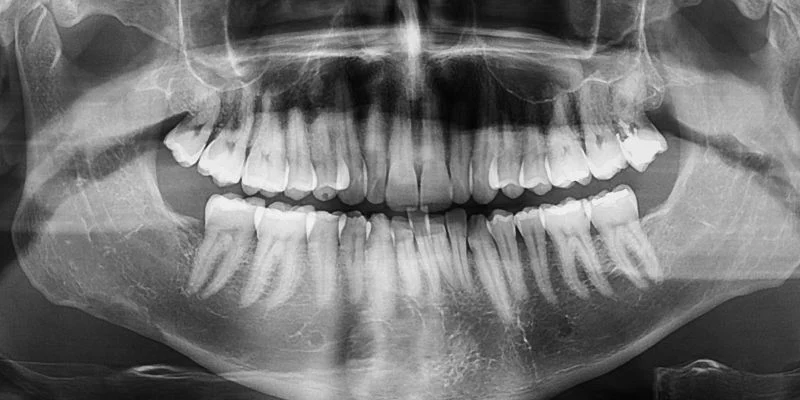

Diagnostic Tools: CBCT, CT, and X-Rays

Dentists use several imaging tools to measure bone density, but they do not all show the same level of detail. Dental cone beam computed tomography (CBCT) has become the most common option for implant planning. CBCT scans create 3D imaging of your jaw with low radiation and high detail.

Traditional computed tomography (CT scans) also provide 3D scans and accurate density data, but they expose you to more radiation and cost more. Dentists now reserve CT for complex cases.

Panoramic X-rays and standard X-rays show bone height and anatomy, but they cannot measure bone density well. They help with screening, not final implant decisions.

CBCT works best because it shows bone shape, volume, and internal structure in one scan.

Studies show the anterior mandible has the highest bone density, while the posterior maxilla has the lowest, which affects implant strategy, as reported in CBCT research on jawbone density differences.